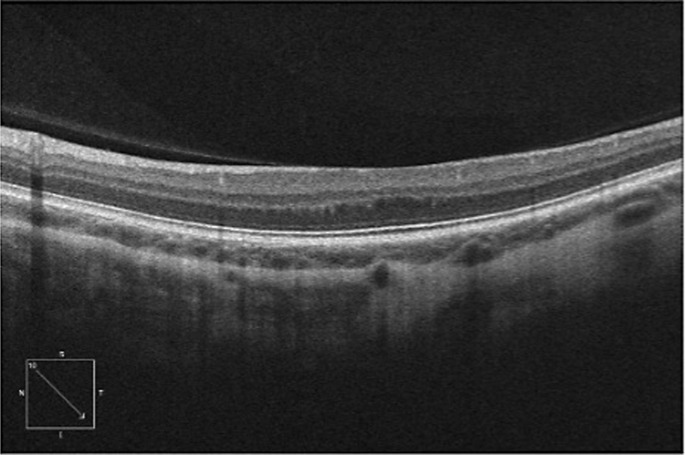

Case presentation: A 67-year-old man with no significant past medical history was referred to our retina clinic with a diagnosis of foveal hypoplasia. He had been experiencing significant vision loss for more than 1 year. OCT demonstrated absence of the foveal depression in both eyes. A subtle ERM was identified in the left eye OCT, but the presence of an ERM in the right eye OCT was equivocal. As such, it was unclear whether flattening of the fovea was attributable to hypoplasia or ERM based on OCT alone. This prompted further investigation with OCTA, which showed the presence of the FAZ in both eyes. The diagnosis of stage 2 ERM OU was made based on OCTA findings. The patient underwent cataract extraction with intraocular lens implantation, pars plana vitrectomy, and ERM peel, which resulted in improvement of visual symptoms and visual acuity. Follow-up OCT showed normalization of the foveal pit in the right eye greater than the left eye.